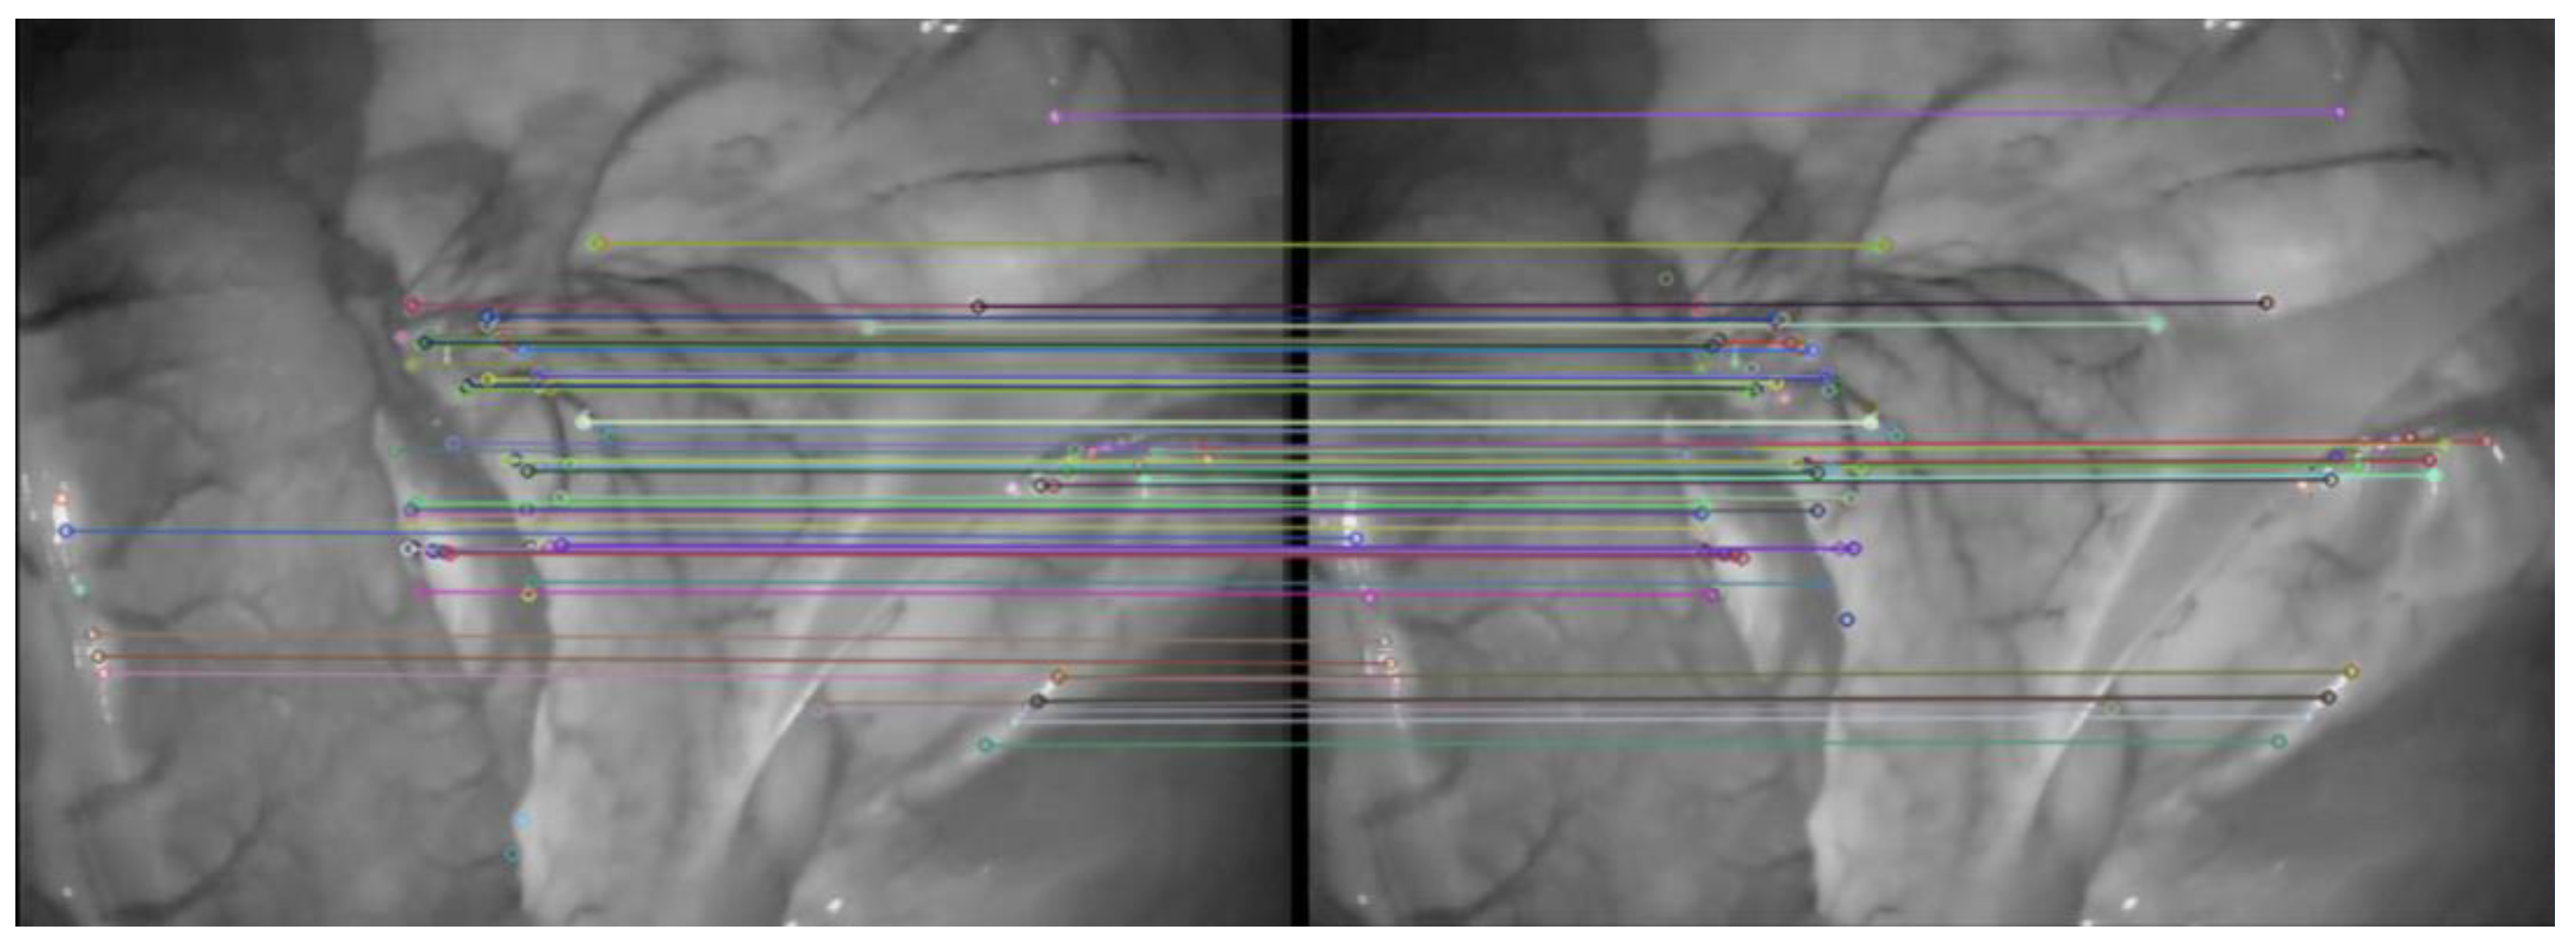

The effect of traditional ORB algorithm and AKAZE-ORB algorithm on extracting feature points of abdominal image frame is shown in Figure 4. The effect of AKAZE-ORB algorithm on abdominal image frame feature point matching is shown in Figure 5.

In order to improve the accuracy of feature matching, this paper uses the symmetry of feature points to quickly eliminate the majority of mis-matched pairs combined with the RANSAC algorithm, as shown in Figure 6.

Figure 5. Feature points matching results obtained by AKAZE-ORB.

Symmetry 14 00185 g005

Figure 6. The results of RANSAC algorithm to identify incorrect matches.

Symmetry 14 00185 g006